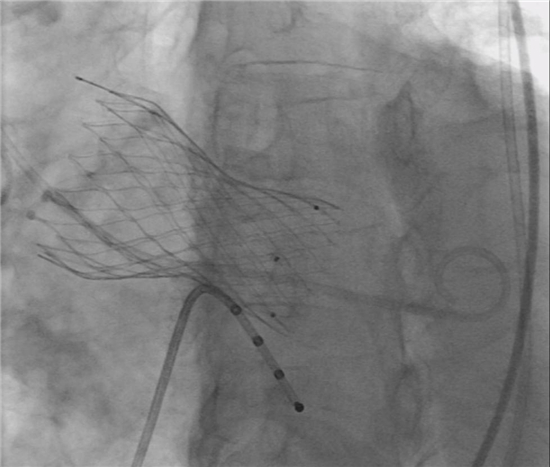

支架瓣膜成功植入体内 供图 南通市第一人民医院

赵老伯的家人托人四处打听,获悉南通市第一人民医院心血管内科已成功开展了微创经导管主动脉瓣置换术(TAVR)。TAVR为主动脉瓣膜病变治疗提供了新的手术选择,只需要通过大腿的血管,就能完成替换损坏主动脉瓣的复杂操作。相对于传统开胸方法,TAVR技术损伤相对轻微,有更低的感染几率、身体的损伤更小、更短的住院时间和更短的恢复时间。

8月1日,南通市第一人民医院心导管室内,一切都有条不紊地进行着。一个多小时的手术结束了,医生认真完成最后一个步骤,为赵老伯身体上唯一的创口消毒贴辅料,右侧大腿上仅5毫米小创口。